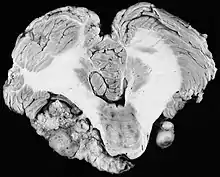

In the early 1900s the mortality rate for VS surgery was in the range of 75 to 85%. Surgeons typically delayed invasive intervention as long as possible as a last resort. Harvey Cushing (1869–1939) is known as 'the father of neurosurgery for VS.' His basic study published in 1917 was entitled Tumors of the Nervus Acusticus and the Syndrome of the Cerebellopontine Angle. Cushing perfected the retrosigmoid surgical approach, and by doing suboccipital craniotomy and subtotal removals he was able to reduce mortality to 4% by 1931. Cushing worked at Brigham Hospital in Boston. An equally famous specialist for VS at Johns Hopkins in Baltimore was Walter E. Dandy (1886–1946), a former pupil of Cushing who advocated total tumor removals. In 1931, he reported a complete removal with preservation of the facial nerve.